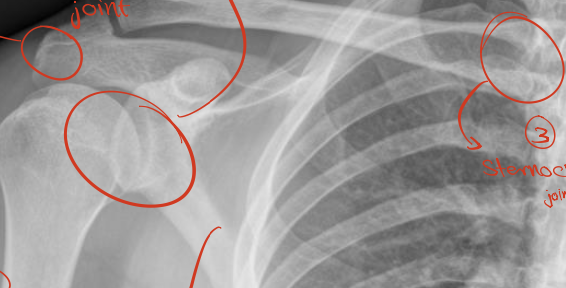

Identify 4 joints ? What view? WHAT IS THAT ?

Sholder Joint

AcromioClavicular Joint

ThoracoScapular Joint

SternoClavicular Joint

— Antero-Posterior View

— X-ray of shoulder